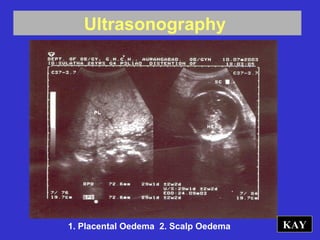

KAY1. Placental Oedema 2. Scalp Oedema